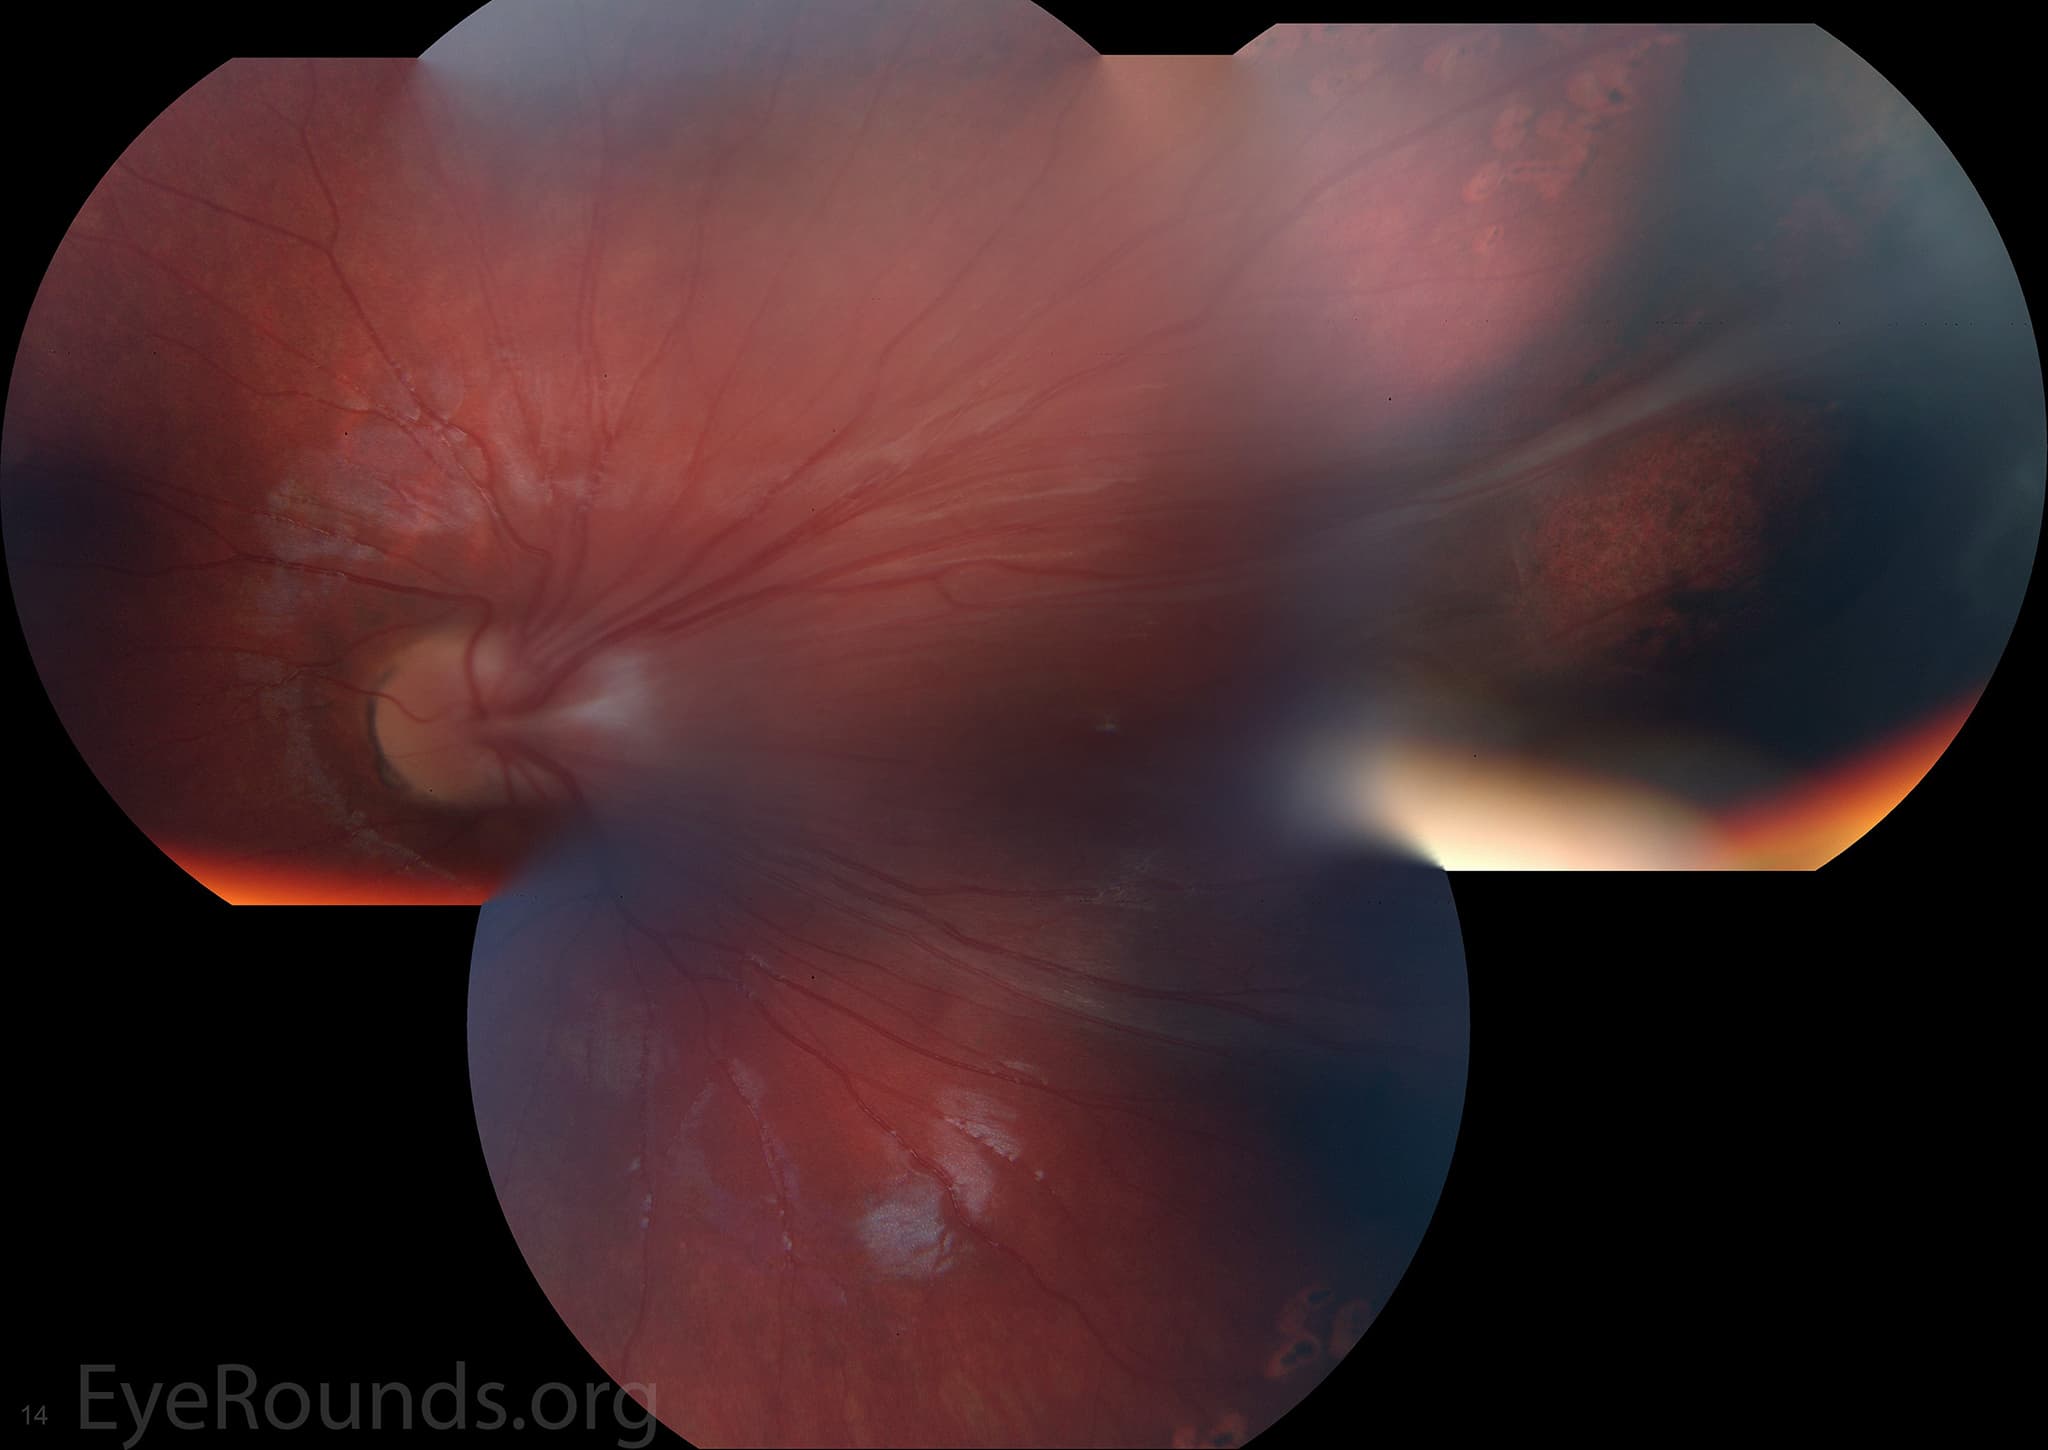

Clinical Images

High-resolution clinical photographs showing various presentations of retinitis pigmentosa.